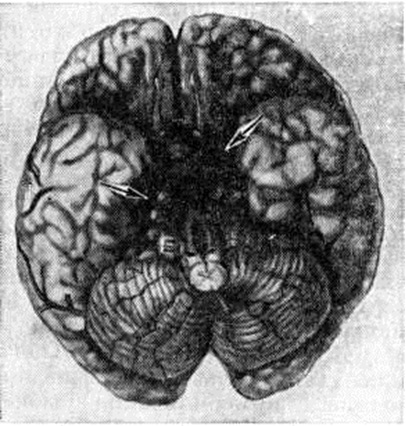

Эпидуральные и субдуральные кровоизлияния в подавляющем большинстве случаев наблюдаются при черепно-мозговой травме (смотри полный свод знаний). Субарахноидальное кровоизлияние возникает наиболее часто вследствие разрыва врождённых мешотчатых или артериовенозных аневризм (смотри полный свод знаний: Аневризма сосудов головного мозга), располагающихся чаще всего в местах разветвления сосудов основания головного мозга (рисунок 1). Некоторые инфекционные болезни, например, грипп (смотри полный свод знаний), геморрагические лихорадки (смотри полный свод знаний) и другие, при тяжёлом течении иногда могут сопровождаться Подоболочечные кровоизлияния Нередко Подоболочечные кровоизлияния возникают в пожилом возрасте у больных атеросклерозом при разрыве склерозированных сосудов мозговых оболочек, а также при хронический воспалительных процессах в твёрдой оболочке мозга, сопровождающихся поражением вен (смотри полный свод знаний: Пахименингит). Развитию Подоболочечные кровоизлияния способствуют заболевания печени, крови, авитаминозы, приводящие к развитию геморрагического синдрома. В ряде случаев Подоболочечные кровоизлияния могут сопутствовать кровоизлияниям в вещество головного мозга при гипертонической болезни, располагаясь часто в задней черепной ямке на поверхности полушарий мозжечка или ствола мозга (рисунок 2, 3). Скопление крови в задней черепной ямке нарушает отток цереброспинальной жидкости и создаёт условия для развития окклюзионной гидроцефалии (смотри полный свод знаний) и отёка мозга (смотри полный свод знаний: Отёк и набухание головного мозга). Вызвать Подоболочечные кровоизлияния могут резкие наклоны туловища, физическая нагрузка, эмоциональное напряжение, сопровождающиеся значительным подъёмом АД.